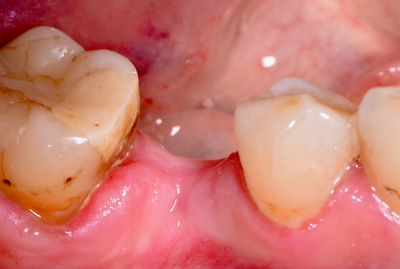

Удаление зуба 26. Установка имплантатов VEGA+ в позиции 25 и 27.

✔️ В позицию зуба 27 установлен VEGA+ RV 4.6x10 mm. Получена первичная стабильность 20 Н/см. Установлен винт-заглушка

✔️В позицию зуба 25 установлен VEGA+ RV 4.1x14 mm. Получена первичная стабильность 50 Н/см. Установлен винт-заглушка.